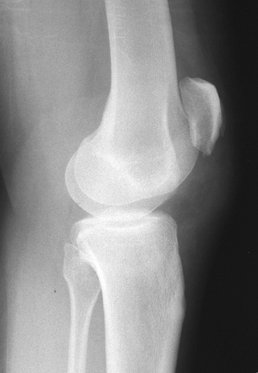

Ontstaat meestal ten gevolge van een indirecte krachtwerking, waarbij de het bovenbeen geforceerd wordt aangespannen met de knie in flexie (bijv. sportblessure). Soms gepaard met systeemafwijkingen, zoals rheumatoide arthritis of het chronisch gebruik van corticosteroiden. Met name krachtsporters, die anabolen gebruiken hebben te maken met spontane ruptuur van de patellapees en/of quadricepspees. Fig.1, fig.2, fig.3, fig.4.

- X-knie (lateraal en AP): hoogstand patella (patella alta) met eventuele avulsie van de patella-onderpool. Bij klinische twijfel is kan een echo uitkomst bieden.